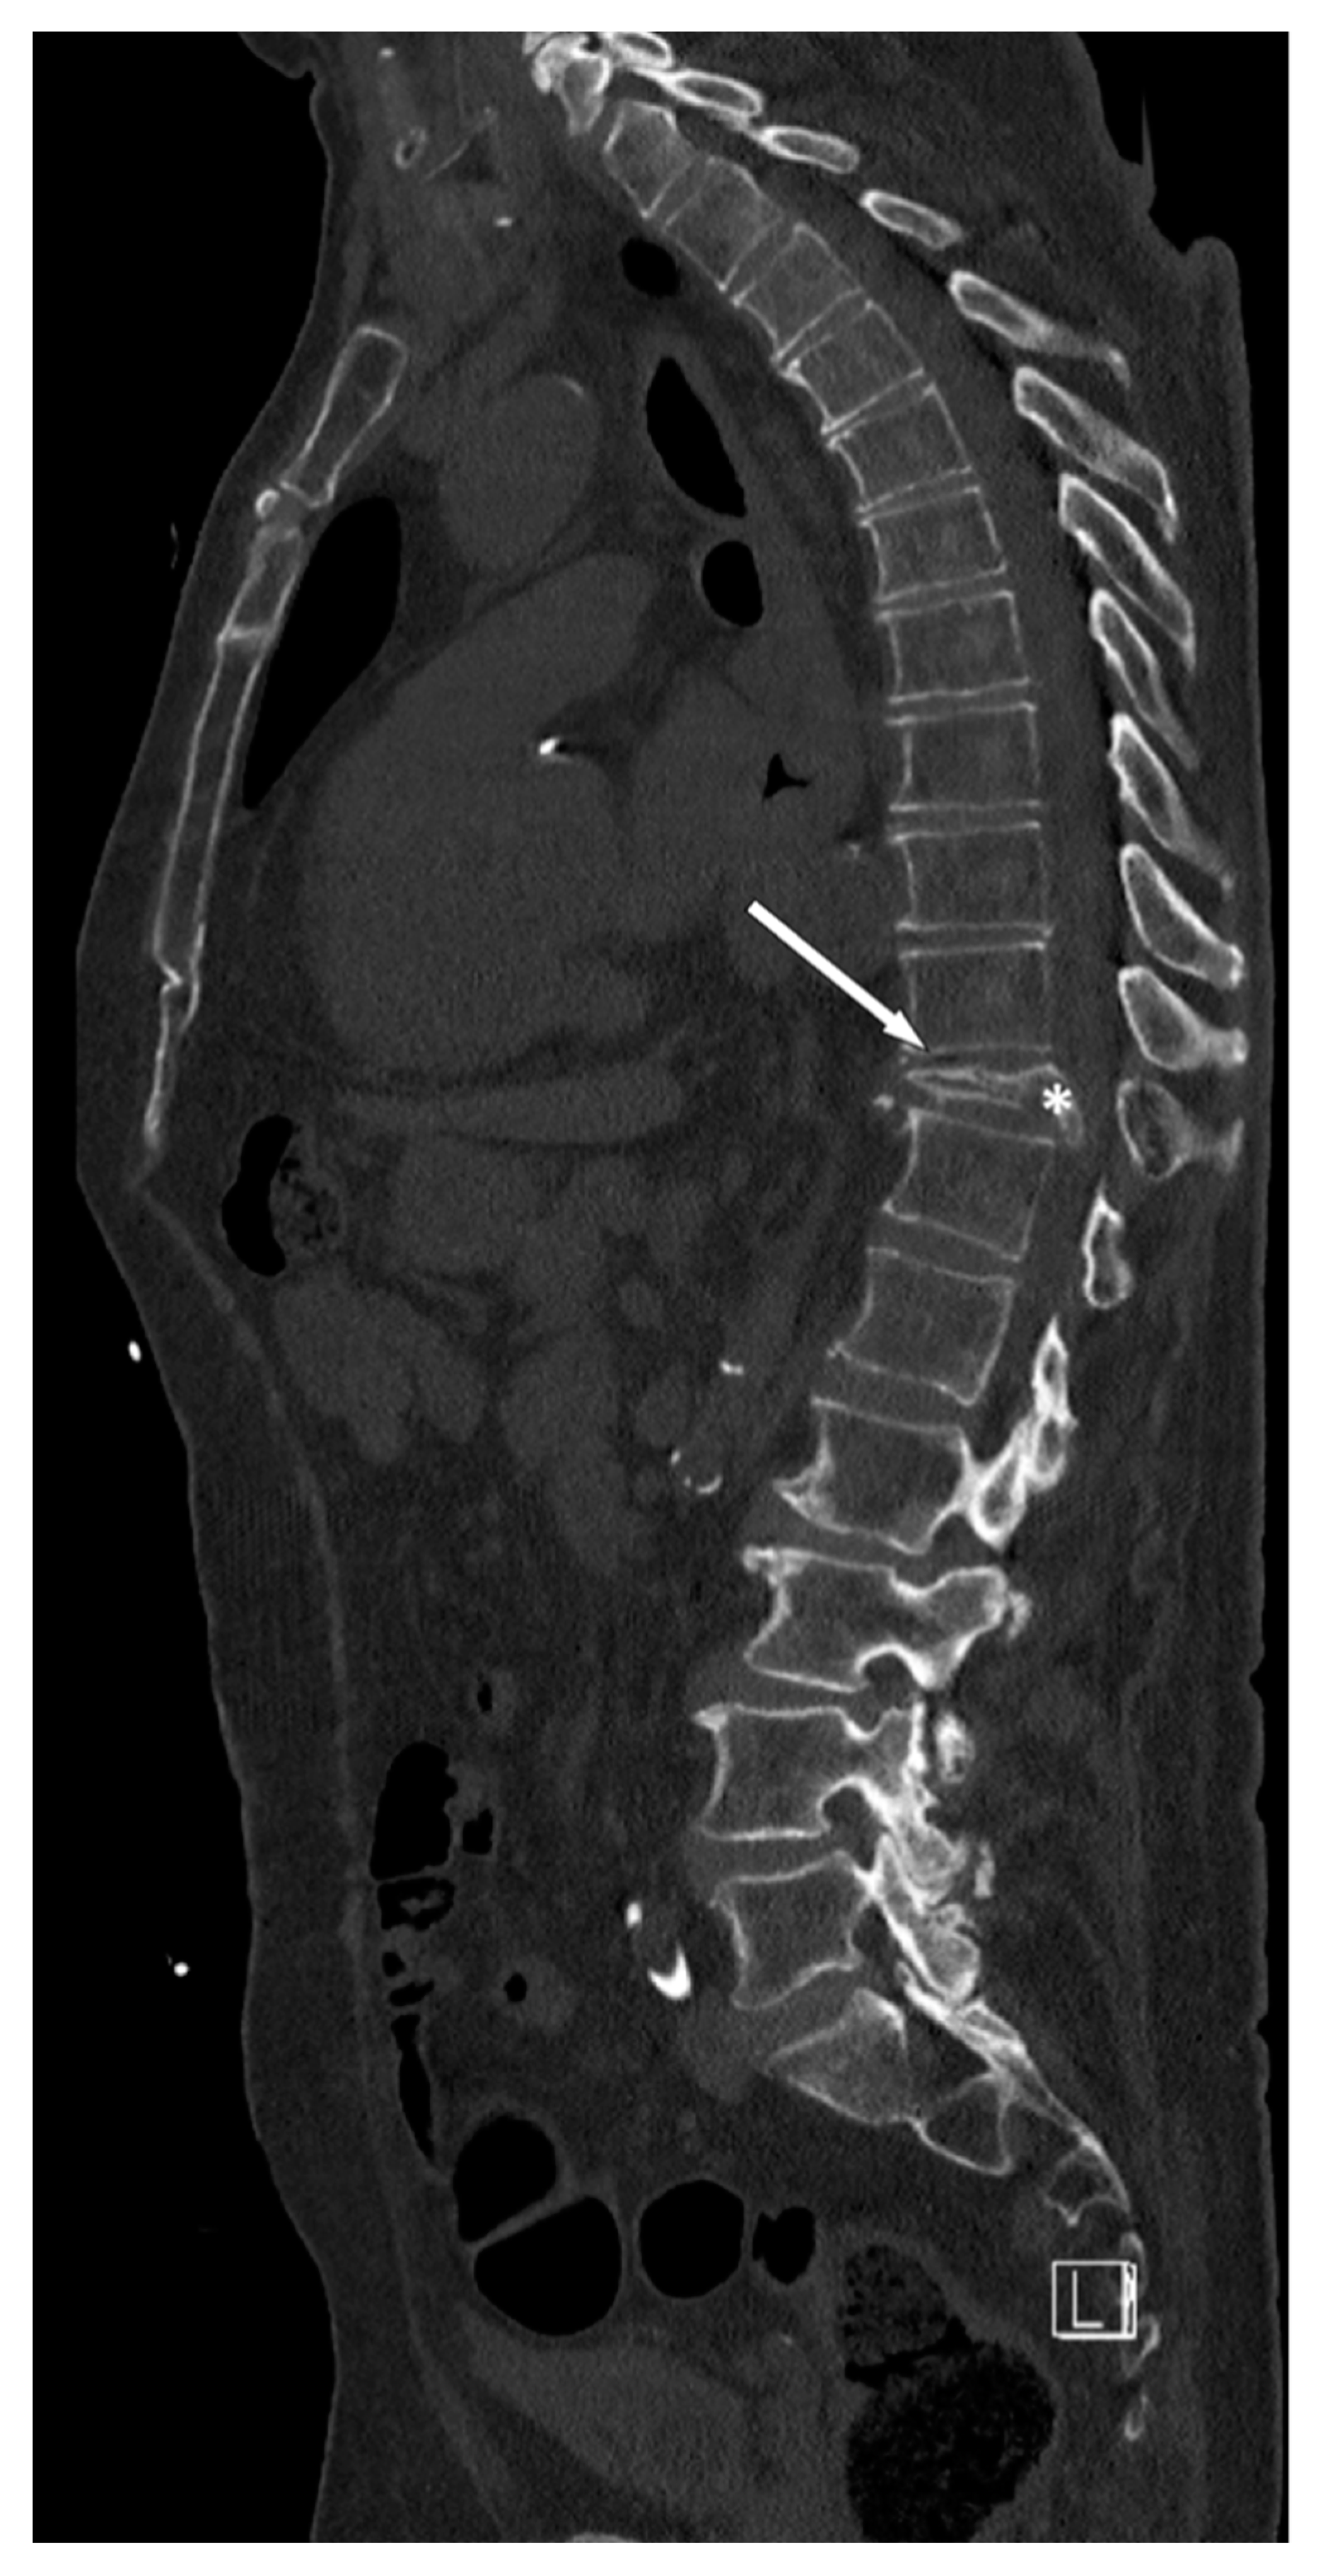

- Maharajan, K.; Hallinan, J.T.P.D.; Sitoula, P.; Pang, Y.H.; Zaw, A.S.; Kumar, N. Unusual presentation of osteoblastoma as vertebra plana—A case report and review of literature. Spine J. 2016, 17, e1–e5. [Google Scholar] [CrossRef]